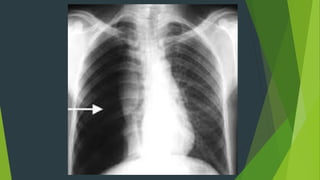

Tràn khí màng phổi

 Phổi bên tràn khí sáng hơn bình

thường, bên trong vùng sáng

không có hình ảnh nhu mô phổi

 Nhu mô phổi bị ép xẹp về phía

rốn phổi

 Cơ hoành bị đẩy xuống thấp

 Tim và khí quản bị đẩy về phía

đối diện